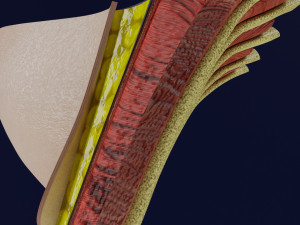

This is a 1:1 scaled model of right breast cut opened in sagittal plane to reveal its internal antomy and histology (schematic). The deeper parts and fascial layers are also depicted to give a very detailed approach to the model. The full layers starting from skin, nipple areola, till intercodtal muscles and ribs are also depicted.